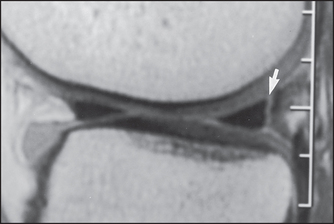

Figures 26.11 and 26.12 show CT scans of changes in the knee.

Figure 26.11 CT scan showing a meniscal tear in the knee joint (arrow) (Resnick DR et al. Internal derangement of joints, 2nd edn. Saunders, 2006.)